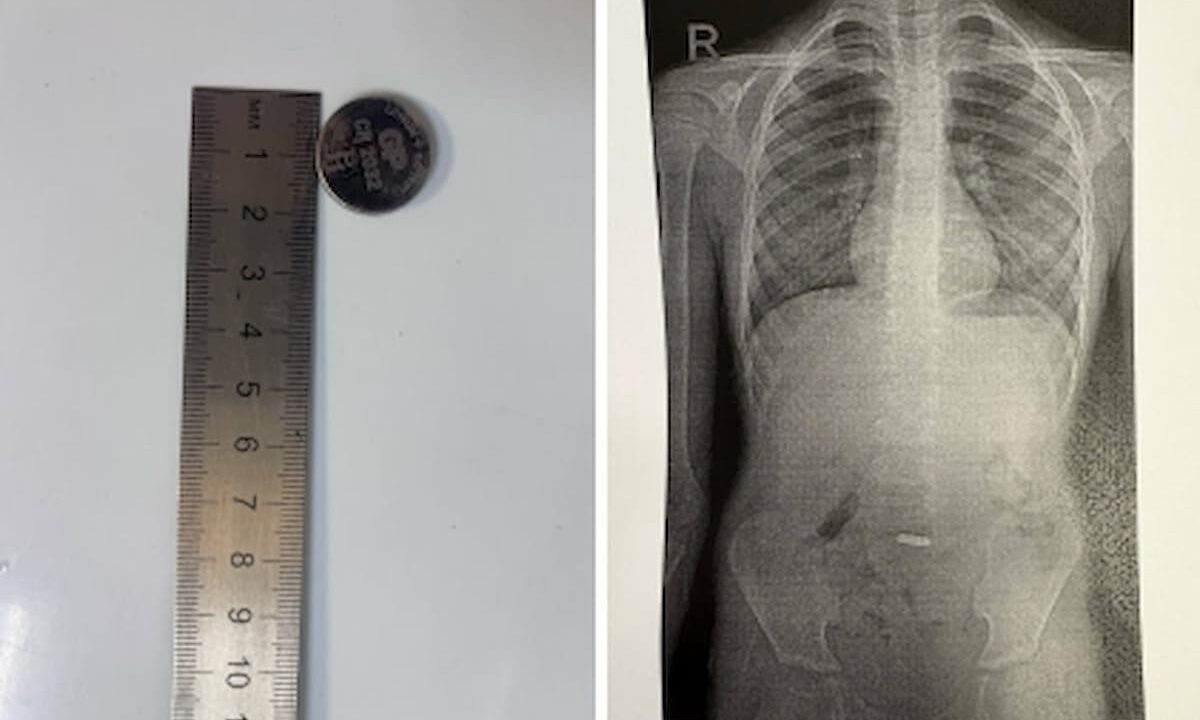

Фото t.me/gorbolnica1nvrsk

В Городскую больницу города-героя поступил 7-летний ребенок с жалобами на тошноту и рвоту. Рентген показал, что маленький пациент случайно проглотил батарейку.

Литиевые батарейки вызывают ожоги слизистых оболочек и некроз тканей и могут привести к перфорации органов уже через 2-4 часа, поэтому достать ее из желудка малыша надо было как можно быстрее.

Медики эндоскопического отделения больницы приступили к манипуляциям. Однако гладкая поверхность батарейки не позволяла зацепить ее обычными щипцами, а спазм пищеводного сфинктера затруднял извлечение: резкие движения могли повредить пищевод или сломать инструмент.

Медики начали «охоту» на батарейку с помощью специального сетчатого инструмента «корзинки-сачка». Во время естественного расслабления сфинктера пищевода батарейку удалось аккуратно извлечь. Операция прошла успешно, жизнь ребенка вне опасности, сообщает пресс-служба Горбольницы № 1 Новороссийска.